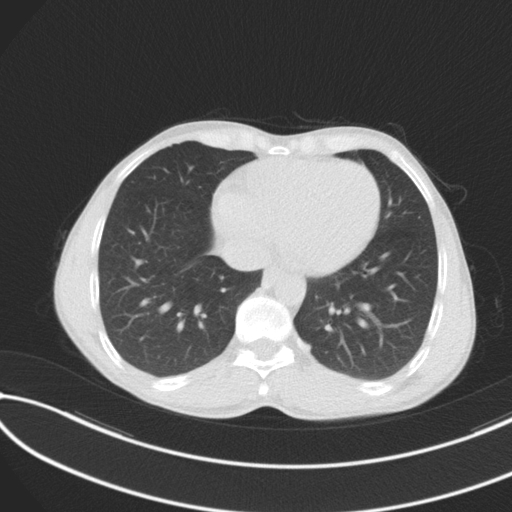

We selected a dataset from Kaggle [10, 11], which includes CT scans of lung cancer and healthy lungs. The dataset has three classes: normal, benign, and malignant. Figure 2 depicts two examples of each class in the dataset.

The images were in DICOM format and were preprocessed to anonymize patient identifiers. The dataset comprises 110 cases, varying in patient age, sex, residential area, and socioeconomic status, among other variables. It contained 1,190 images, although we detected and removed duplicate files, with a total of 1,054 unique images. These are distributed as shown in Table 1.